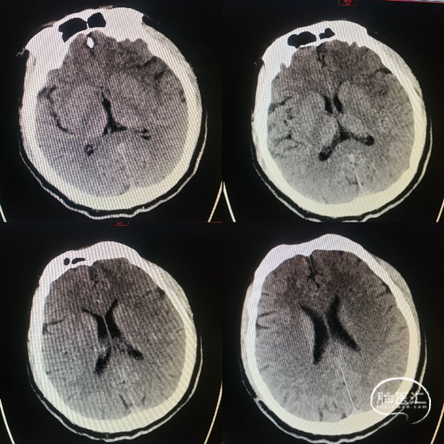

术前影像学

复查颅脑CT颞叶梗死表现:

核心梗死体积33.43ml,低灌注体积153.98ml,Mismatch120.55ml。